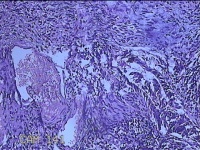

性别

女

年龄

34岁

临床诊断

宫颈上皮内肿瘤?

一般病史

月经干净7天,宫颈HPv18,12亚型阳性。

标本名称

大体所见

灰白粉红色组织0.5x0.3x0.2cm一块。

图2